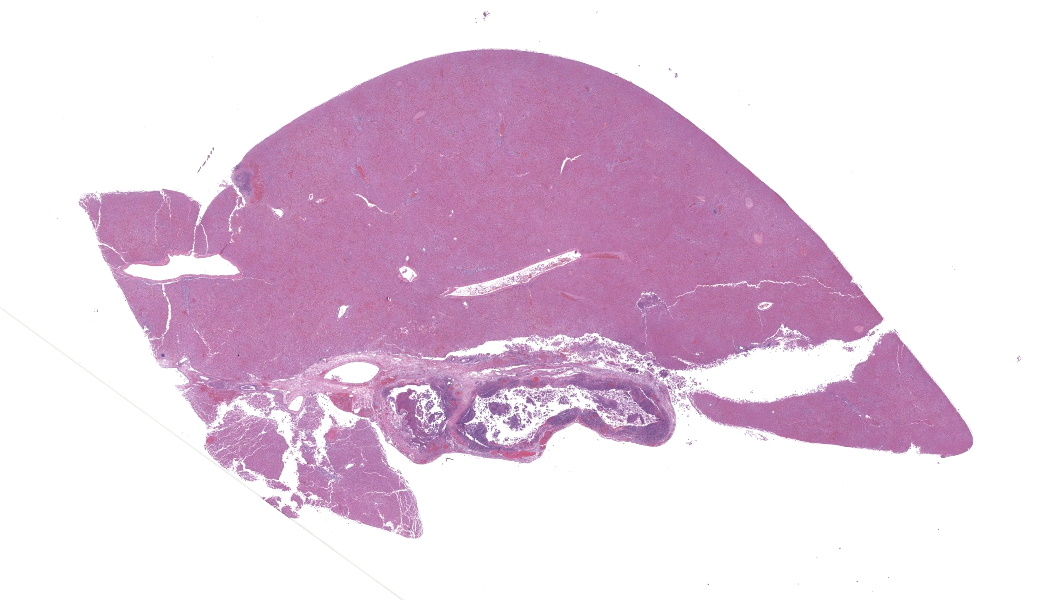

Microscopic Description:

Gallbladder and liver: The gallbladder and adjacent portal tracts are effaced by multifocal to coalescing areas of coagulative and lytic necrosis admixed with foci of suppurative inflammation. The gallbladder is transmurally severely expanded by numerous neutrophils, scattered lymphocytes and histiocytes, abundant polymerized fibrin, necrotic debris eosinophilic proteinaceous fluid (edema), extravasated red blood cells (hemorrhage), and mats of extracellular rod-shaped bacteria (bacilli). Multifocally, blood vessels in the gallbladder are distorted by endothelial and/or mural necrosis and innumerable bacilli. Some vessels are partially occluded by fibrin and bacterial thrombi. Remaining intact vessels are congested. There is marked loss of gallbladder epithelium characterized by hypereosinophilia and loss of nuclear detail (necrosis), occasionally seen sloughing into the lumen admixed with neutrophils, fibrin, and red blood cells. Throughout the liver, bile ducts and portal vasculature undergo similar changes of varying severity (Fig 2). Bacilli are located extracellularly within portal areas and within sinusoids or intracellularly within macrophages. There are moderate, acute, multifocal loss of hepatocellular detail admixed with areas of fragmented chromatin and karyolytic debris (coagulative and lytic necrosis). Remaining hepatocytes are mildly to moderately swollen by small to medium-sized, round, clear, cytoplasmic vacuoles.